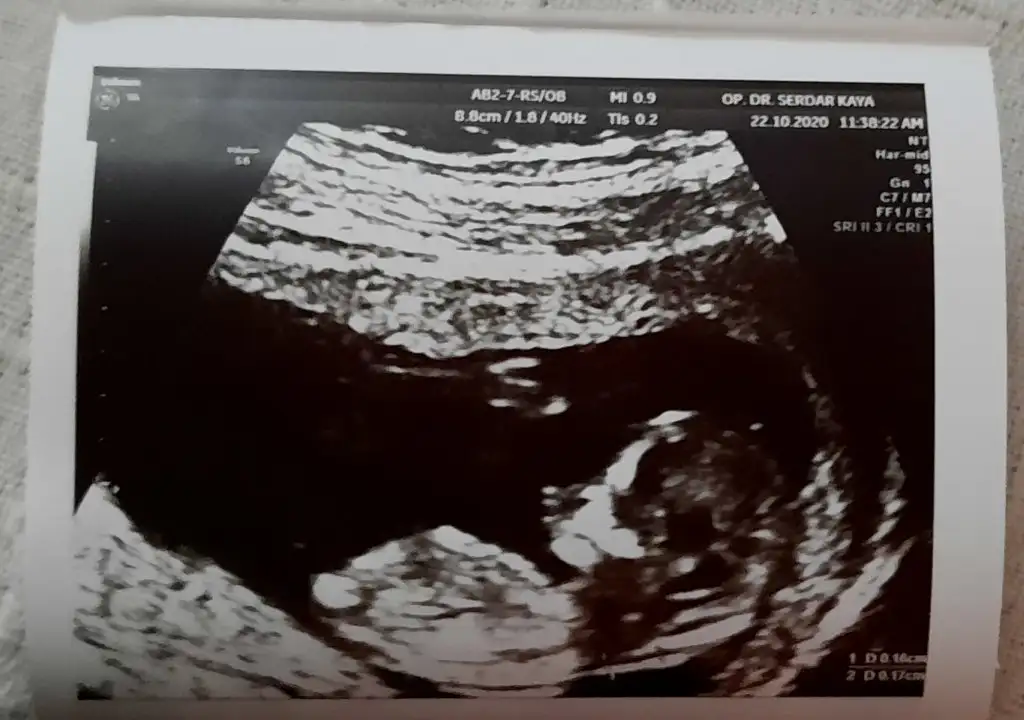

Eklentiler

• 20201023_150518.webp

34,4 KB · Görüntüleme: 84

• 20201023_150459.webp

40,8 KB · Görüntüleme: 83

Doktor erkek dedi ama 12.hafta olunca ben emin olamadım. Pipi fotosu da vermiş, ona da bakınca çok emin olamıyorum. Belli bir aya dek benzer gittiği için genital organlar, belki yanılmıştır diyorum..kız istediğim için..umarım bir ay sonra, yanılmışım, kızmış der doktor..